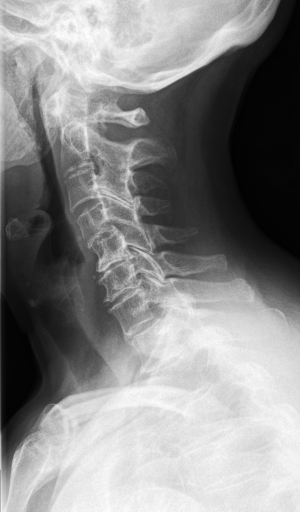

Figure 3 shows some samples images from IRMA dates along with their corresponding IRMA codes.